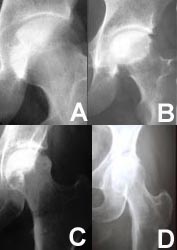

In the earliest stage of the disease, x-rays appear normal and the diagnosis is made using MRI. Once it can be seen on x-ray, it is not actually the dead bone that can be seen but the healing response of the living bone to the area of necrosis. The advanced stages of ON begin when the dead bone starts to fail mechanically through a process of microfractures of the bone. Eventually, this will result in damage to the other side of the joint, requiring major joint reconstruction.

These x-rays of the hip show the different stages of the disease. At first (stage I), there are no detectable changes on x-ray (fig A). In stage II, there are some changes but the surface is still intact (fig B). As the disease progresses, the surace begins to collapse (fig C) until, finally, the integrity of the joint is destroyed (fig D).

In the more advanced stages of the disease and/or when more of the joint is damaged, it is less likely that the natural joint can be preserved. Fortunately, joint replacement procedures today are highly successful, even in the relatively young patients affected by ON. It is always the physicians desire to preserve the normal joint whenever possible. Unfortunately many patients do not visit the doctor until their joint has an advanced stage of the disease.